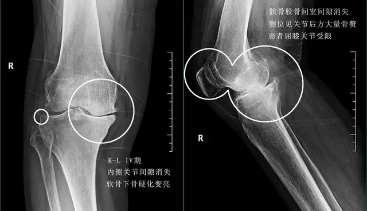

前面已经说到骨关节炎会导致骨赘的形成以及关节间隙的狭窄,所以我们依靠膝关节x片子来初步判断骨关节炎的病情,通常我们采用K_L分期判断病情。

四期患者:4期的骨关节炎患者关节已经出现了严重的畸形,这个时期患者会非常的痛苦,关节会有严重的畸形,通常不能行走很长的距离,有一些患者甚至行走500米就疼痛难忍了。而且患者通常会出现比较明显的休息痛以及静息痛,什么意思呢?就是说,不动也痛。

此时我们只有通过进行关节置换手术的办法,才能帮助患者来解决痛苦。医生也知道很多患者不想做全膝关节置换术,所以说现在也研究出来单髁的置换手术,也算是一种保膝治疗。